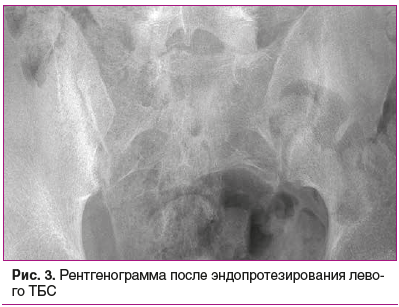

Посредством проводимой терапии в январе 2021 г. удалось достигнуть низкой активности заболевания (ASDASCRP — 0,97, BASDAI — 2,8). После достижения низкой активности заболевания в феврале 2021 г. пациенту успешно проведено эндопротезирование левого ТБС (рис. 3).